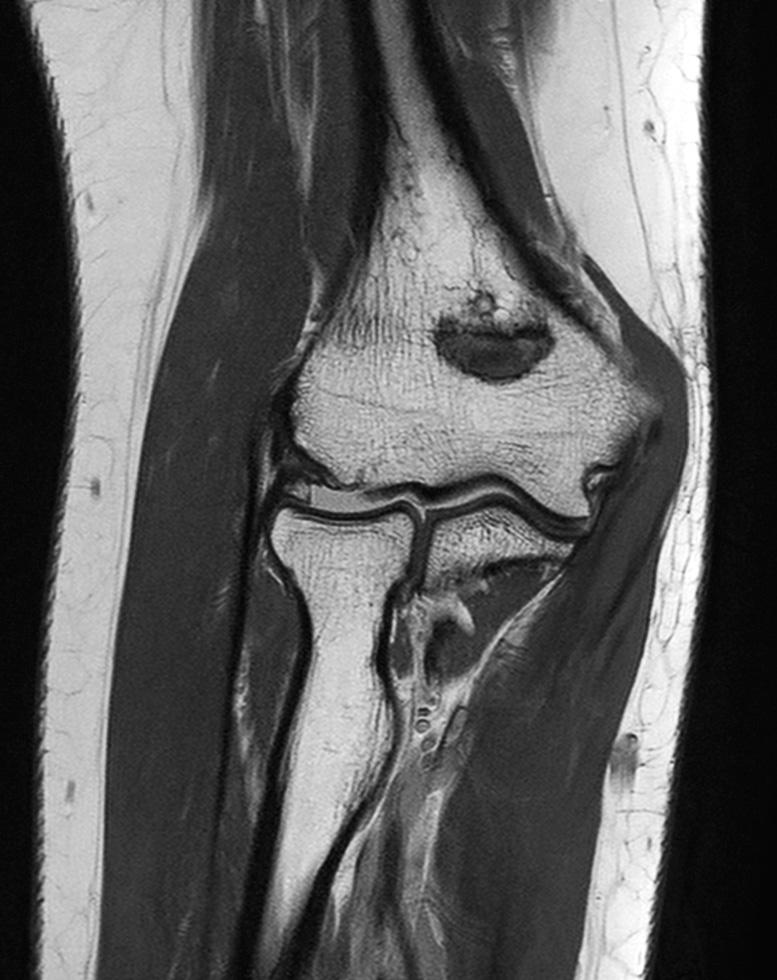

Elbow Imaging